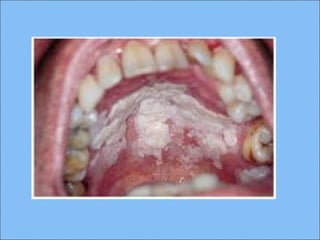

Estomatitis nicotínica (paladar deEstomatitis nicotínica (paladar de

fumador)fumador)

Uno de los cambios más comunes en el

el paladar duro

CLINICAMENTECLINICAMENTE

Hombres de 45 años de edad

Debido a un largo periodo de exposición

al calor, la mucosa palatal llega a ser de

un color gris difuso o blanco

Numerosas pápulas ligeramente elevadas

con un punto rojo en su centro:

dilatación de los conductos de las

glándulas salivales menores

La mucosa que cubre las pápulas a

menudo se presenta más blanca que la del

epitelio circundante.